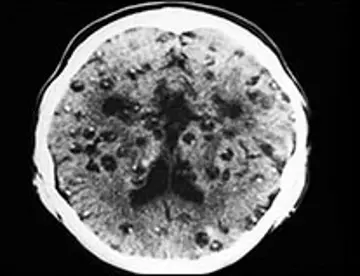

بیماری های عفونی - صفحه 15